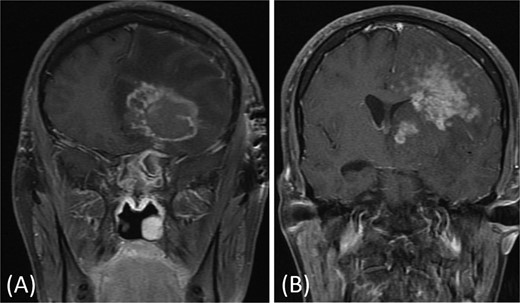

A 31-year-old man, who is a known case of Gilbert syndrome, presented to the rhinology clinic with a 1-year history of progressive bilateral nasal obstruction and left eye proptosis. The patient had previously undergone FESS twice outside the hospital for allergic fungal rhinosinusitis, with the most recent procedure having been performed two years before his presentation at the clinic. On examination, the nasal endoscopy showed extensive nasal polyposis, while the neurological examinations were normal. The CT scan and MRI revealed a mass in the left ethmoid cavity with an erosion of the lamina papyracea, extending into the extraconal fat and obstructing the frontal recess with mucosal thickening (Fig. 3). The patient was therefore suspected of having recurrent fungal rhinosinusitis and underwent FESS for debulking and to obtain a biopsy. Postoperatively, the histopathological results confirmed the diagnosis of CGIFRS, and A. flavus was found in the tissue culture. The patient was then started on oral voriconazole for 3 months.

Paranasal CT scan without contrast a mass in the left ethmoid cavity with erosion of the lamina papyracea (arrow).